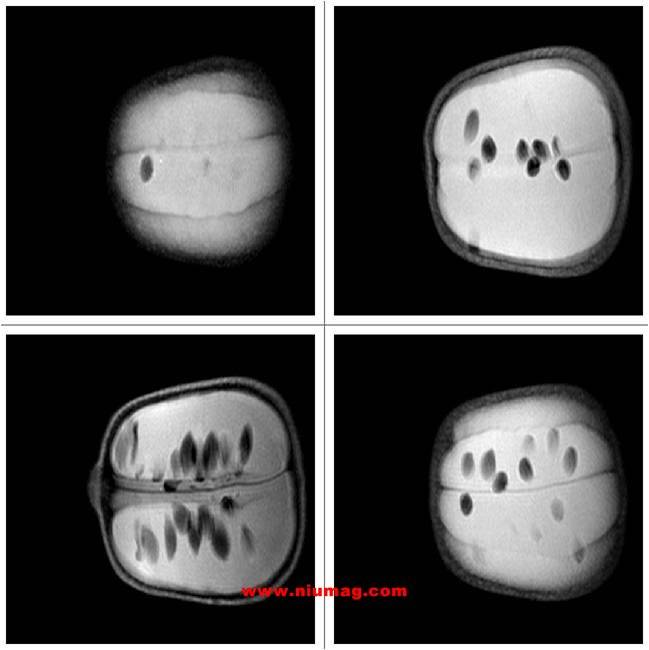

玉米核磁共振多層成像圖-橫斷位

玉米核磁共振多層成像圖-失狀位